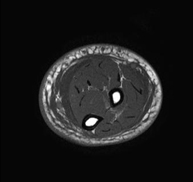

Exploració ideal per estudiar les lesions en músculs isquiotibials i quàdriceps, sovint lesionats en esportistes. També permet una bona valoració de tendons i de nervis perifèrics. La durada aproximada és de 20 minuts. No utilitza radiació ionitzan. - RM de Genoll

Exploració per estudiar lesions a l'articulació, com trencaments dels meniscals i dels lligaments creuats (únicament es poden detectar amb aquesta prova), condropatia o desgast del cartílag i moltes altres alteracions derivades de l'activitat esportiva i dels canvis degeneratius (osteoartrosi). La durada aproximada és de 18 minuts. No utilitza radiació ionitzant. - RM de Cama

Exploració per a l'estudi de les lesions en petites estructures anatòmiques de l'articulació, com ara el cartílag i els meniscs, principalment els ja operats. L'estudi ve precedit per una injecció de contrast a l'interior de l'articulació, realitzada sota control de raigs X. La durada total dels dos procediments és de 50 minuts. - Artro-RM de Turmell